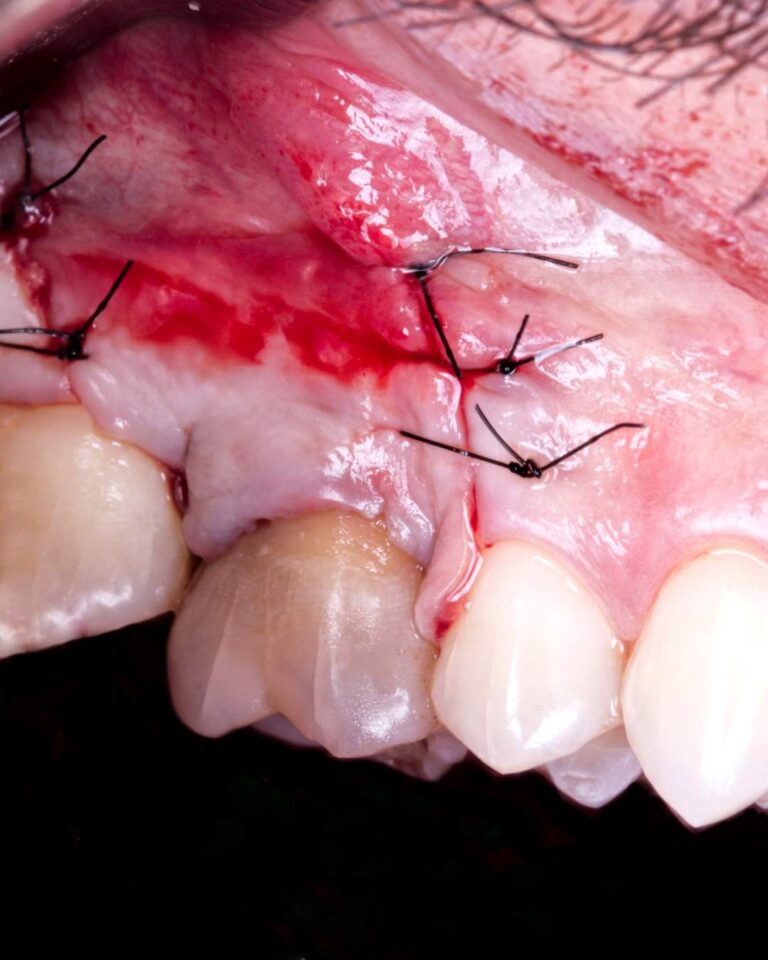

Cirurgia apical para remoção de quisto